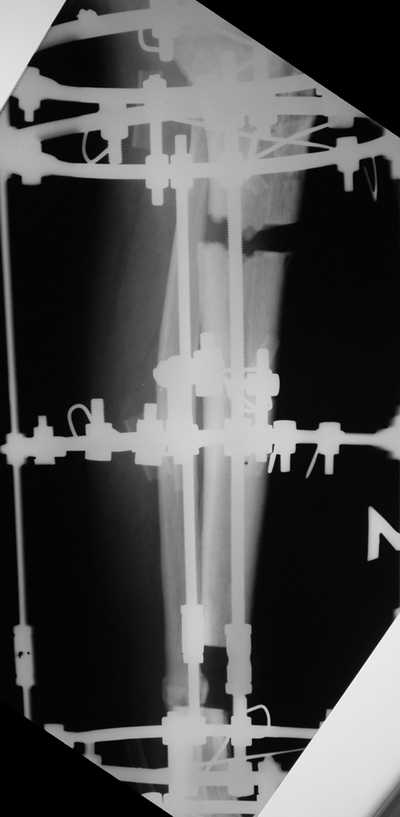

Мужчина, 33 года, резекция б\б кости по поводу остеомиелита после открытого перелома. Стандартная методика билокального остеосинтеза (рис 1 и 2). В конце удлинения выявилось неудовлетворительное взиморасположение перемещенного фрагмента и дистального отломка (рис 3). Планирование (рис 4).

Адаптация отломков гексаподом за 5 дней (рис 5). Замена гексапода на обычные штанги (рис 6 и 7)